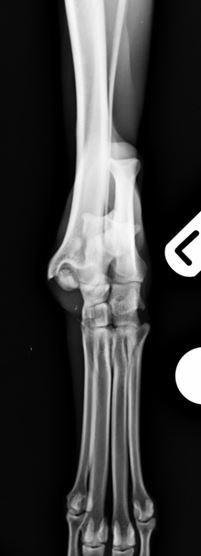

Radiographs revealed a comminuted non-reducible fracture of the medial talar ridge and a displaced fracture of the distal fibula.

Figure 1. Comminuted talar and distal fibular fractures lateral view

Figure 2. Comminuted talar and distal fibular fractures craniocaudal view